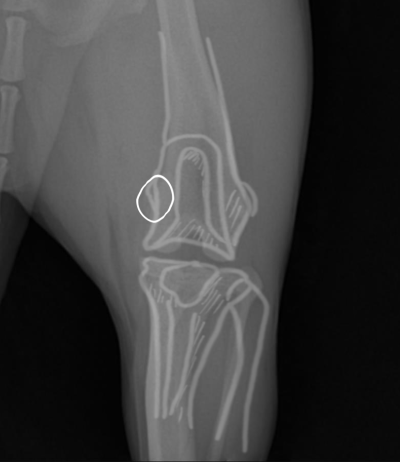

환자의 수술 전 / 수술 후 사진입니다.

환자의 수술 전 / 수술 후 사진입니다. 활차구 성형술을 진행하여, 얕게 있던 고랑을 깊게 파 주었습니다.

이후 지대중첩술과 경골조면변위술을 진행하여 돌아가 있던 무릎의 각도를 잡아주었습니다

환자의 수술 직후 사진입니다.

수술 직 후, 내측으로 빠져있던 슬개골이 정상 위치로 돌아온 것이 확인됩니다.